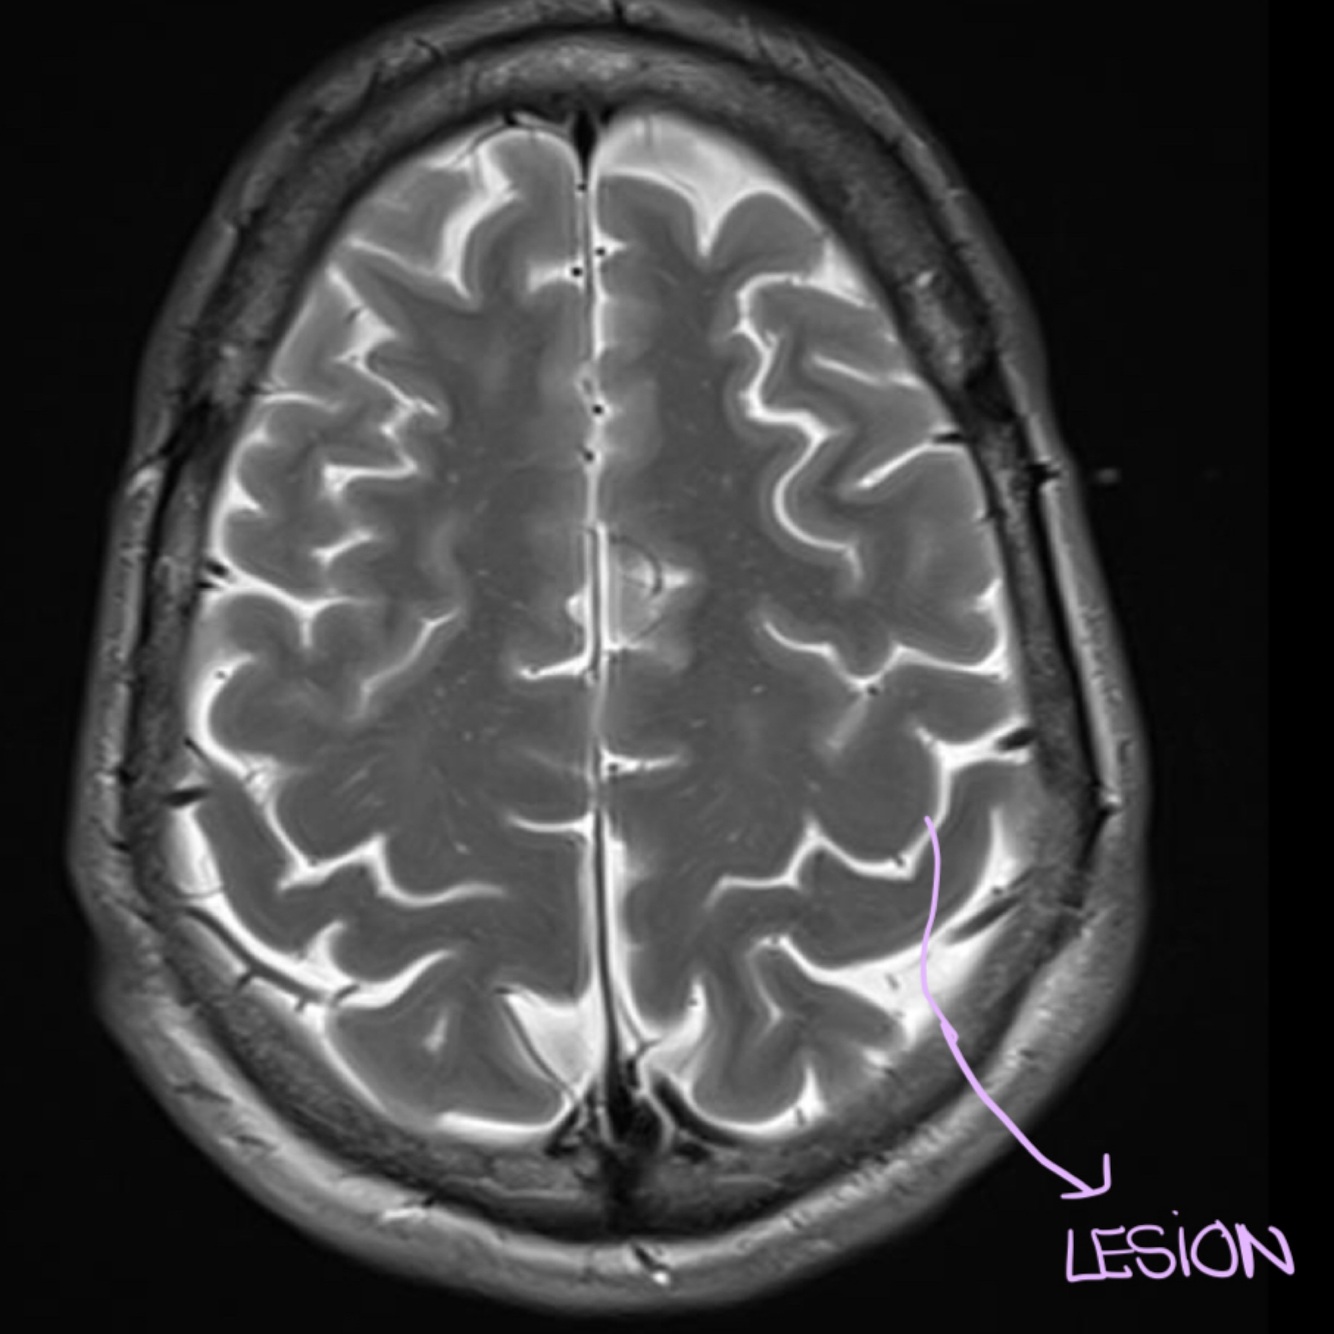

A lesion in this area might cause, problems in the contralateral… (hand/leg)

HAND (more lateral)